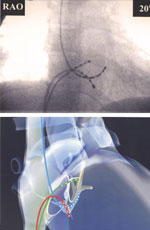

Чреспищеводная электрокардиостимуляция

Чреспищеводная электрокардиостимуляция – неинвазивная процедура, направленная на получение записи биологических потенциалов с внешней поверхности сердца, используя при этом специальный пищеводный электроды и регистрационную аппаратуру. Проведение специальных видов стимуляции для изучения электрофизиологических свойств проводящей системы, миокарда предсердий и желудочков. Выявление субстратов аритмии, их локализации и электрофизиологических характеристик. Контроль лекарственной и/или нефармакологической терапии. Ненвазивное электрофизиологическое исследование сердца (ЧПЭФИ) Опыт применения ЧПЭС в кардиологии насчитывает более 30 лет. В нашей стране первое сообщение о применении ЧПЭС у больных с ишемической болезнью сердца появилось в научной медицинской литературе более 10 лет назад. За этот период времени отношение к любому методу исследования уже носит устойчивый характер, а возможности самого метода хорошо изучены. Следует сказать, что отношение кардиологов к методу ЧПЭС в течение этого времени менялось в зависимости от развития самой кардиологии и технических возможностей применяемых стимуляторов. Повышенный интерес к этому методу в настоящее время обусловлен с одной стороны, бурным развитием самой кардиологии, как науки, в частности ее аритмологии, а также появлением современных стимуляторов с хорошими техническими характеристиками, позволяющими производить исследование с минимальными неприятными ощущениями для больного. Применение ЧПЭФИ помогает решить три основные задачи:диагностика, лечение (терапевтическое, подбор антиаритмических препаратов) и прогнозирование во многих клинических ситуациях.

Область применения ЧПЭС в кардиологии

У больных ишемической болезнью сердца:

1) диагностика коронарной недостаточности; 2) определение степени (функционального класса) коронарной недостаточности, 3) диагностика безболевой ишемии миокарда; 4) выделение группы больных с ишемической болезнью сердца (ИБС), имеющих высокий риск внезапной сердечной смерти; 5) подбор оптимальной эффективной дозы антиангинального препарата и наиболее рационального приема его в течение суток; 6) выделение группы больных, которым наиболее целесообразно проведение коронароангиографии и последующего оперативного лечения ИБС; 7) верификация крупноочаговых рубцовых изменений миокарда у больных с синдромом WPW; 8) одновременная регистрация эхокардиограммы по программе стресс ЭхоКГ при проведении дозированной частотной нагрузки при ЧПЭС позволяет диагности¬ровать скрытые формы коронарной и миокардиальной недостаточности.